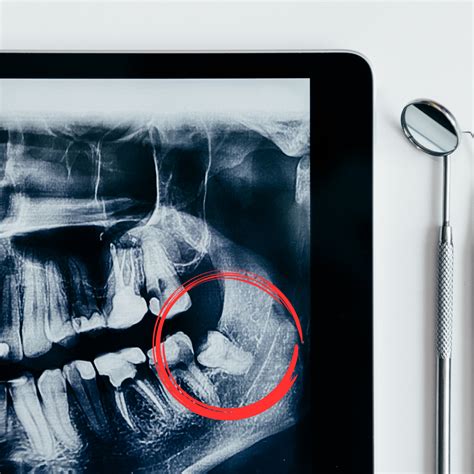

El riesgo de sufrir infección de muela del juicio es mayor cuando el cordal no ha podido emerger totalmente por falta de espacio. Pero, incluso si han erupcionado bien, estas muelas tienen más posibilidades de sufrir lesiones que el resto. A continuación, veremos las dos causas más comunes de infección en la muela del juicio:

- Infección por Pericoronaritis: Es una inflamación del tejido que rodea a la muela del juicio, que es más común cuando la muela no ha erupcionado del todo. La razón es que alrededor de ella se crea una capa de tejido blando que suele acumular restos de alimentos. En consecuencia, se convierte en un nido para las bacterias que suele derivar en infecciones.

Si te están saliendo las muelas del juicio, es importante programar una cita con el dentista para analizar si será necesaria la extracción de las muelas del juicio. Esto dependerá de varios factores, incluido si tus muelas del juicio están impactadas. Es absolutamente necesario extraer una muela del juicio impactada porque causará una inflamación adicional alrededor de las encías y un daño severo a los molares.